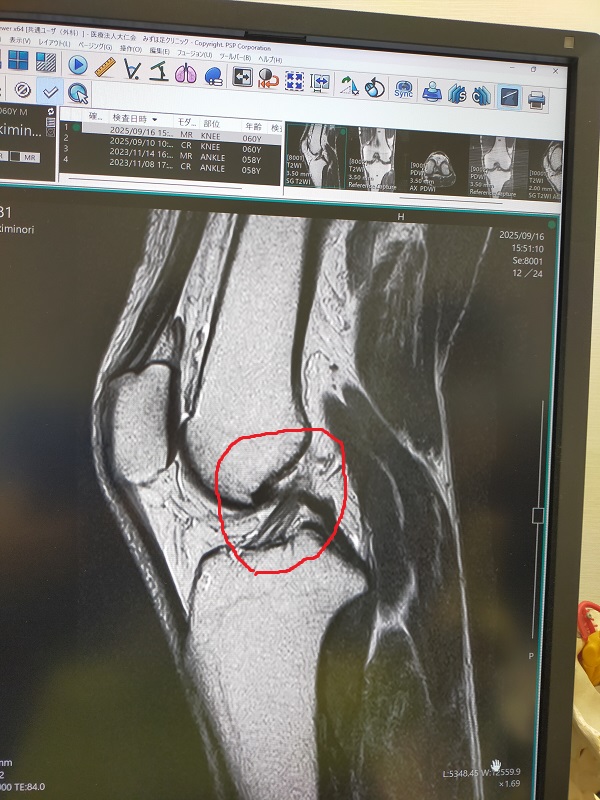

MRI 診断結果    ..キミ     返信

.jpg / 117.4KB 左膝のMRIからの診断結果

半月板や靭帯に悪い箇所はなし

左膝の外側の筋?に少し水が溜まっている(青)

骨と骨の間にも薄く水が溜まっている(赤)

重症ではないとの診断でした

深刻な状況ではないことがわかったので一安心

気分的にはプラスに振れました